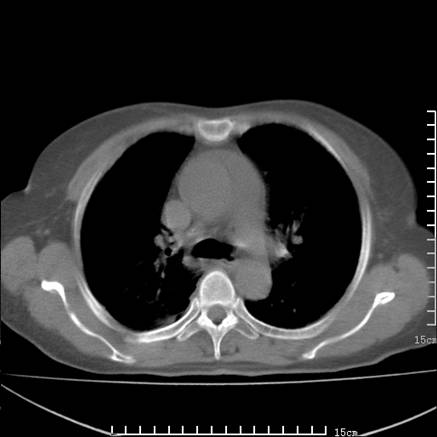

女,王某,58岁,咳嗽三个月余,基层医院二个月前诊为肺结核,用抗结核药二个月无明显疗效。

心包积液致肺瘀血.右侧周围型肺癌伴肺内转移,中间裂积液,叶间胸膜肥厚.右上肺大泡,右侧胸膜肥厚.

双肺继发型tb,心功能不全并肺淤血、心包、双侧叶间裂积液,肺大泡,右下胸膜肥厚钙化。

支持  双肺继发型tb,心功能不全并肺淤血、心包、双侧叶间裂积液,肺大泡,右下胸膜肥厚钙化。